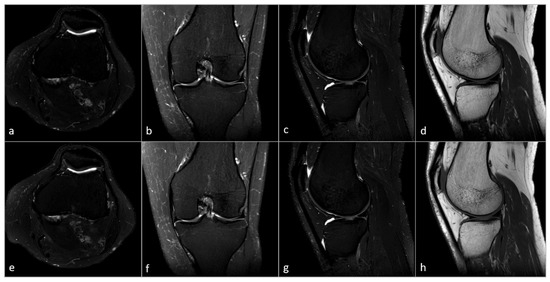

2. Material and Methods

2.2. MRI Acquisition

2.3. MRI Reconstruction